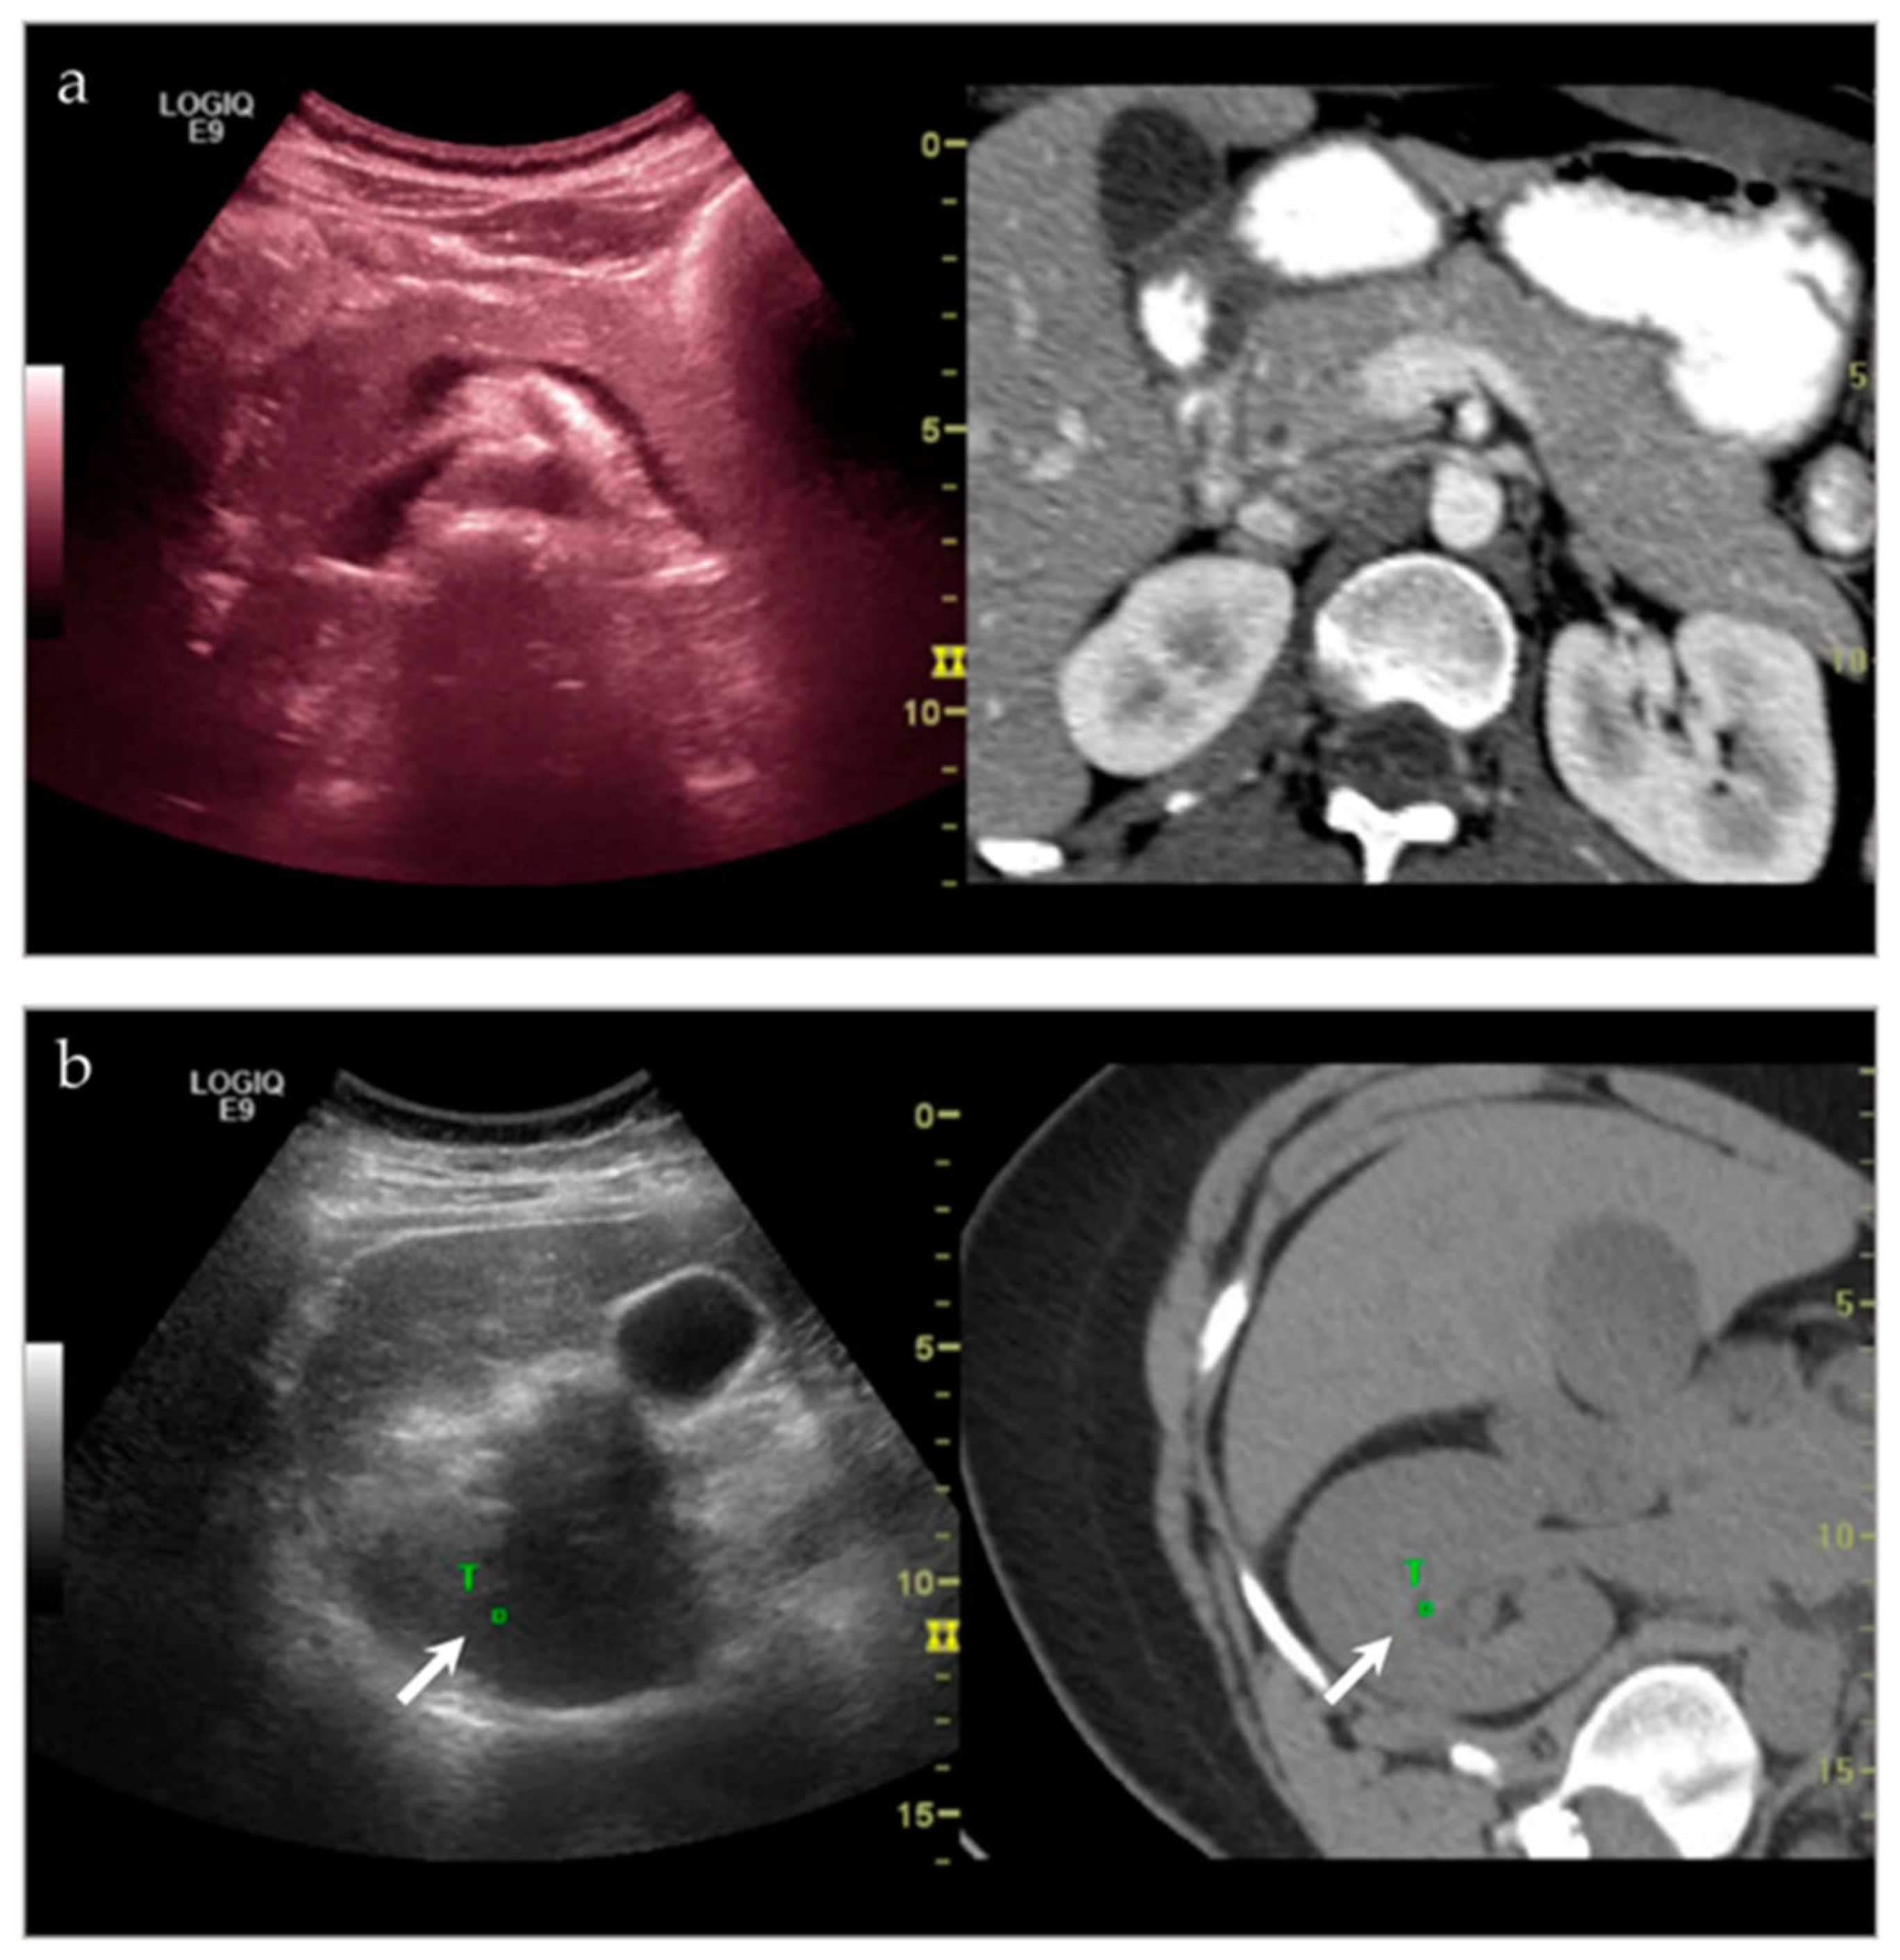

3.2.4. Targeted Percutaneous Lesion Biopsy and/or Aspiration

| NA **/F | Right psoas muscle | US-CT fusion | Abscess | Infection |